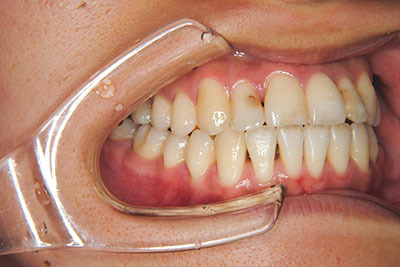

おとなの方でも矯正治療をあきらめないでください!

いくら歯が動き易くとも、本人がやる気でなければ効果は出ませんし、むし歯発生のリスクも高まります。おとなの方は顎の成長が終わっているため、治療の計画が立てやすいとも言えます。「もう大人だから…」とあきらめず、一度ご相談ください。